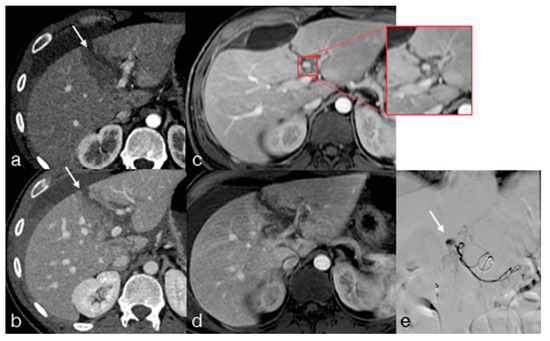

- Iacobellis, F.; Iacobellis, F.; Scaglione, M.; Scaglione, M.; Brillantino, A.; Brillantino, A.; Scuderi, M.G.; Scuderi, M.G.; Giurazza, F.; Giurazza, F.; et al. The additional value of the arterial phase in the CT assessment of liver vascular injuries after high-energy blunt trauma. Emerg. Radiol. 2019, 26, 647–654. [Google Scholar] [CrossRef]

- Østerballe, L.; Helgstrand, F.; Axelsen, T.; Hillingsø, J.; Svendsen, L.B. Hepatic pseudoaneurysm after traumatic liver injury; is CT follow-up warranted. J. Trauma Manag. Outcomes 2014, 8, 1–5. [Google Scholar] [CrossRef]